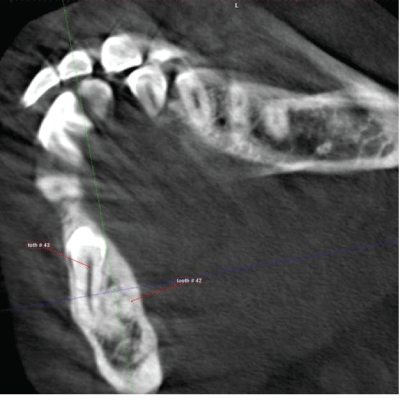

The right mandibular lateral incisor (#42) impacted lingual to impacted tooth # 43 and the crown is directed distally below the apices of first and second premolar , with this pathway of impaction it seems it will be difficult to exposes the tooth to be aligned in the proper location (Figures 4-6).

Figure 4: CBCT, sagittal view showing impacted right mandibular lateral incisor the crown directed distally.

Figure 5: CBCT, axial view showing impacted right mandibular canine.

Figure 6: CBCT, axial view showing impacted right mandibular lateral incisor in almost horizontal position at the level of root apices of adjacent teeth.